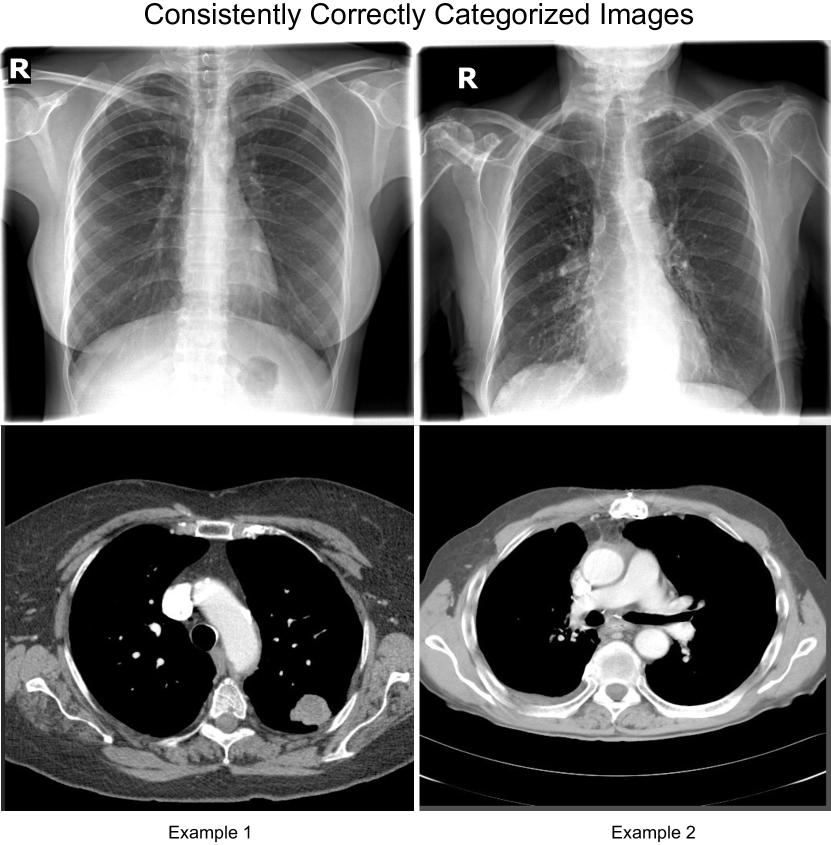

Finally, we analyze the results qualitatively. In Figure 3, we show sample examples of PA X-ray images and corresponding generated CT scans that are consistently correctly categorized. We find that data points that most consistently get categorized correctly represent patients with clear X-rays with little noise and no internal devices. In these cases, the CT generator also produces realistic CT images.